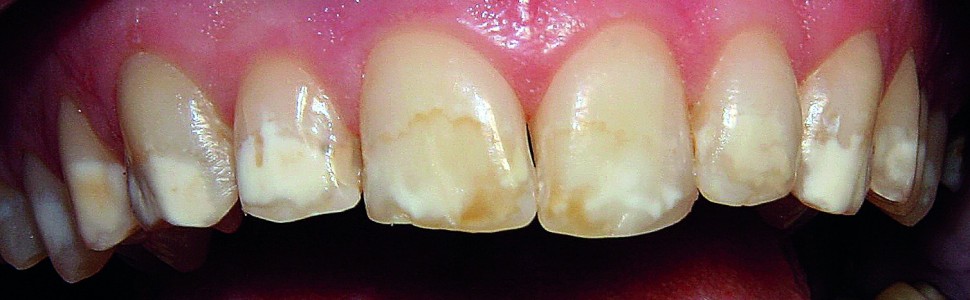

In recent years, it has been noted that there is an increasing incidence of enamel defects in children and adolescents. Given patients' increasing esthetical demands, dentists frequently face requests for treating of these types of lesions. The most common form of developmental defects of enamel are opacities. Enamel white spots lesions, especially on the front teeth, can impact patients' quality of life, therefore it is important to identify the enamel defect early and choose the appropriate preventive and therapeutic method. The purpose of this article is to provide a description cases of five patients in developmental age who have used the resin infiltration method supported by remineralisation in the treatment of developmental defects of enamel in the opacity type (opacities) and present clinical results with up to 12-month follow-up.